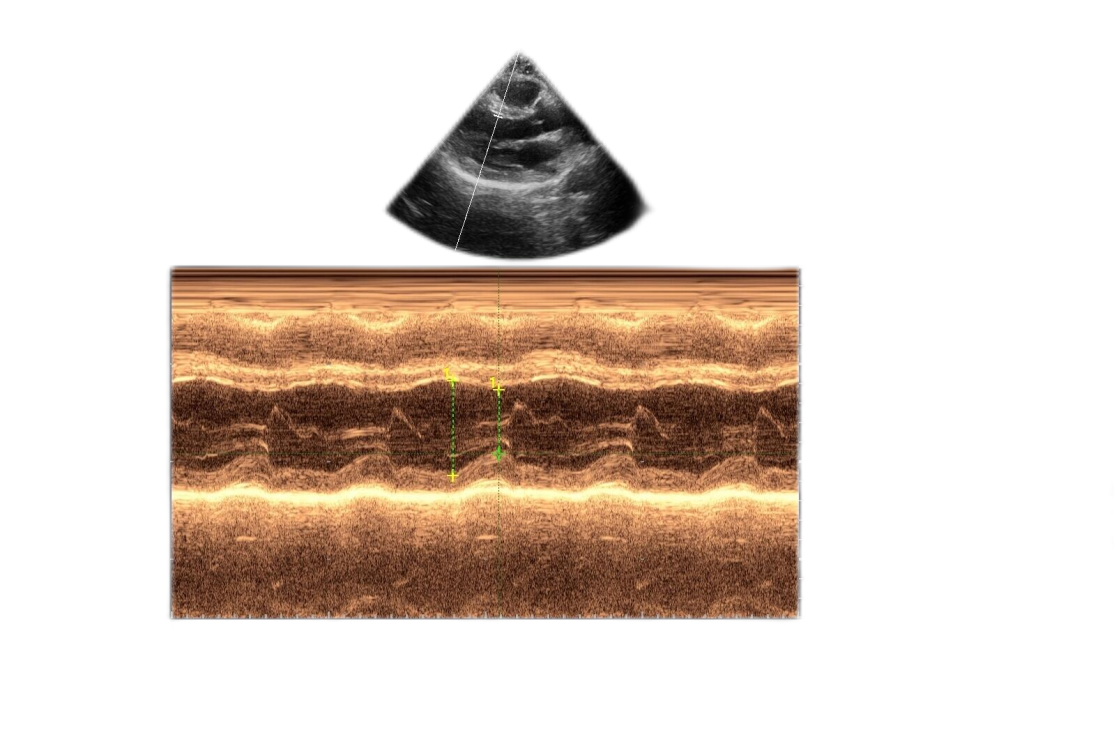

所以彩超和彩色电视机是不一样的,图像不一定是彩色的。同时,彩超医师偶尔会使用伪彩功能,使黑白图像变成彩色,可以在某些情况下改善人眼对不同回声强度的敏感度,从主观上增加了显示信号的动态范围,增强图像边界的可识别程度,提高超声对疾病的检出率。

“伪彩”功能